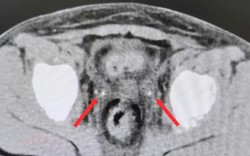

• Ngày càng nhiều chị em còn trẻ đã mắc ung thư cổ tử cung, bác sĩ khuyên: 4 món này ngon đấy nhưng ăn ít lại!

Ngày càng nhiều chị em còn trẻ đã mắc ung thư cổ tử cung, bác sĩ khuyên: 4 món này ngon đấy nhưng ăn ít lại!